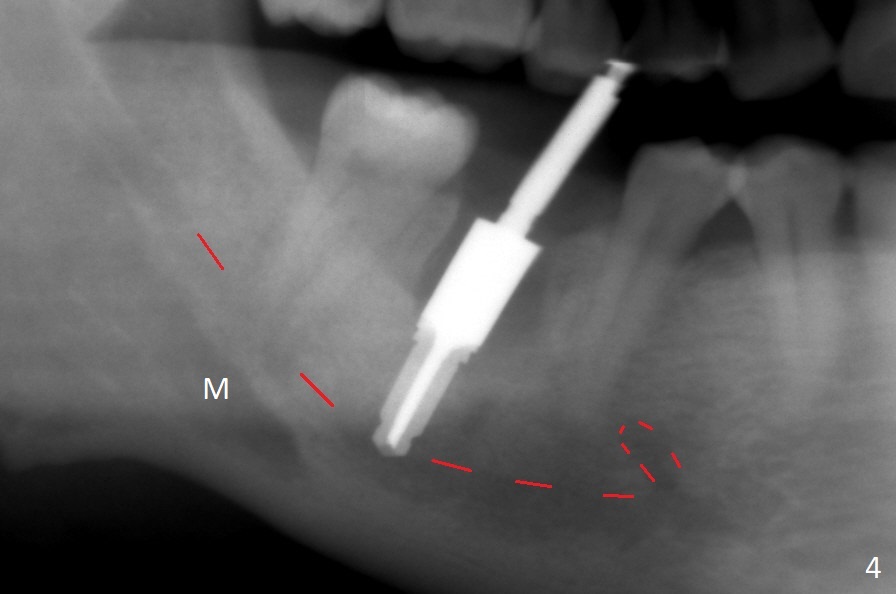

After the tooth #30 is extracted, the socket is 18 mm deep and the lingual plate is 4 mm tall. With hemorrhage, visibility of the socket, especially the bottom, is poor. The septum is almost completely defective. Following removal of the most buccal portion of the septum, osteotomy is initiated as buccal as possible, but it is mesial (Fig.1). In spite of effort to move the osteotomy distal, the osteotomy remains mesial and superficial (Fig.2 with 5 mm tap drill). Pain control is poor with infiltration. It appears that the smaller osteotomy (Fig.2 yellow line) may have extended close to the superior border of the Inferior Alveolar Canal (red line). It appears that there is 8.5 mm bone distal with ~ 2 mm clearance. After mandibular block, a new osteotomy is made distal; when a 3.8 mm drill is being used, there is hemorrhage from the osteotomy with apparent violation of the Canal integrity (Fig.3,4). But hemostasis is achieved with gauze pressure. A 5x13 mm implant is placed superficially (Fig.5) with a trace of the previous osteotomy (yellow line) and deep space created by the mesial osteotomy (*). Apparently the pathological and iatrogenic defects are filled with allograft (Fig.6 *). Guided surgery could have avoided the mesial osteotomy.

Fortunately no paresthesia is reported postop. Why is the Inferior Alveolar Canal not violated? Fig.7 is a coronal section of CBCT taken for a 40-year-old man at the lower 1st molar (at the septum). At the region, the Canal (brown circle) is close to the lingual plate (L). Because of severe bone loss of the lingual plate of this case (Fig.8 *), osteotomy is intentionally created buccal (green). The deep osteotomy may not contact the Canal, while the hemorrhage may stem from the medullary space (M in Fig.4,7). Bone morphology at the coronal end of the implant apparently changes 4 months postop, suggesting osteointegration (Fig.9). Impression is taken. Bone density around the implant at the crest seems to increase (Fig.10), while there is no soft tissue deficiency 10 months post cementation (Fig.11). The bone appears to regenerate toward the abutment, particularly distally, 14.5 months post cementation (Fig.12). Periimplantitis develops (bleeding on water pik and erythematous and tender buccal gingiva) 1 year 7 months post cementation (Fig.13,14). The 1st three threads are exposed (*). Bone graft with PRF and 6-month membrane or Cytoplast will be needed. Pain disappears 3 days of oral antibiotic. The gingiva looks healthy 1 month later when he returns for bone graft (Fig.15). But the lingual gingival cuff is not so healthy when the crown/abutment is removed (Fig.16 <). Bone graft is not done. For those patients with suboptimal oral hygiene, implants should be placed as low as possible, better with guide for precision.